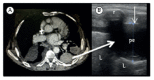

Lung ultrasound in the evaluation of pleural effusion